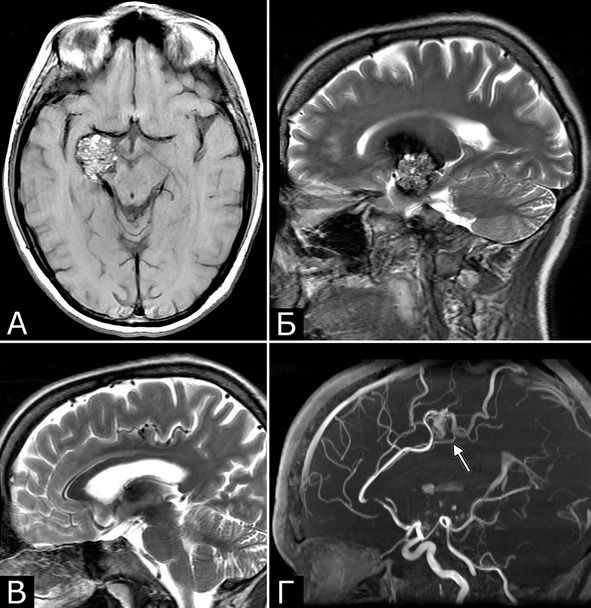

Сочетание каверномы с АВМ выявлено у двух больных, причем в обоих случаях клинические проявления заболевания были обусловлены АВМ, а кавернома явилась случайной находкой (рис. 1).

Рис. 1. Б-ная Г., 27 лет. Сочетанная сосудистая патология мозга: КМ передне-медиальных отделов височной доли справа (А – МРТ, режим Т1; Б – МРТ, режим Т2); АВМ медиальных отделов лобно-теменной области справа (В – МРТ, режим Т2; Г – МРТ-АГ). Клиническое течение: редкие вторично-генерализованные судорожные эпилептические припадки, начинающиеся с судорог в левых конечностях